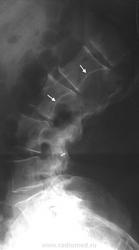

Элсберга-Дайка симптом (рентг.) - рентгенологически определяемое расширение интерпедикулярного расстояния и деформация (вогнутость) внутренних поверхностей ножек дуг. Характерен для длительно существующих объемных процессов позвоночного канала (опухоль, дермоидная киста, дермальный синус).

(С. A. Elsberg, 1871-1948, американский хирург  S. С. Dyke, совр. англ. патолог) рентгенологически определяемая деформация ножек дуг позвонков и увеличение расстояния между ножками дуг; признак опухоли спинного мозга.

При опухолях, растущих из позвоночника, и невриномах на рентгенограммах в ряде случаев обнаруживаются патологические изменения со стороны тел позвонков (остеопороз, компрессия позвонка и др.). Нередко выявляется синдром Эльсберга - Дайка, для которого характерна неправильная форма корней дужек позвонков и асимметрия расстояния между ними и остистым отростком.